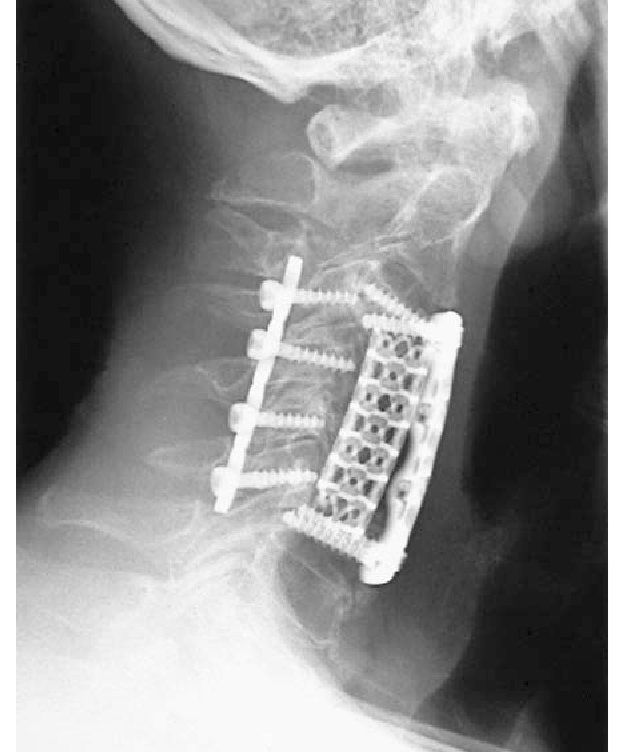

Титановый каркас для позвоночника — это медицинское устройство, используемое для лечения заболеваний позвоночника, и один из наиболее часто используемых имплантатов.Титановые каркасы для позвоночника, обычно изготавливаемые из титанового сплава, могут лечить различные заболевания позвоночника, такие как сколиоз, межпозвоночные грыжи и расщепление позвоночника, поддерживая позвонки и восстанавливая нормальную анатомию и функцию позвоночника.

Титановые каркасы для позвоночника характеризуются высокой прочностью, коррозионной стойкостью, биосовместимостью, ковкостью, легкостью формовки и наглядностью.Эти особенности делают титановые кейджи для позвоночника одним из наиболее важных инструментов для лечения заболеваний позвоночника.

Кроме того, титановые каркасы для позвоночника бывают различных форм и размеров, что позволяет врачам формировать их в соответствии с формой и размером, необходимыми для лучшей поддержки тела позвонка.Титановый кейдж для позвоночника имеет хорошую рентгенопроницаемость для послеоперационного наблюдения и осмотра.

Использование титанового каркаса для позвоночника требует хирургического вмешательства, при котором хирург имплантирует каркас в позвоночное пространство, а затем заполняет его костной золой или искусственным костным материалом, чтобы стимулировать рост костей и стабильность позвоночника.После операции пациентам необходимо пройти надлежащую реабилитацию, чтобы помочь имплантату лучше срастись и восстановить нормальную функцию позвоночника.